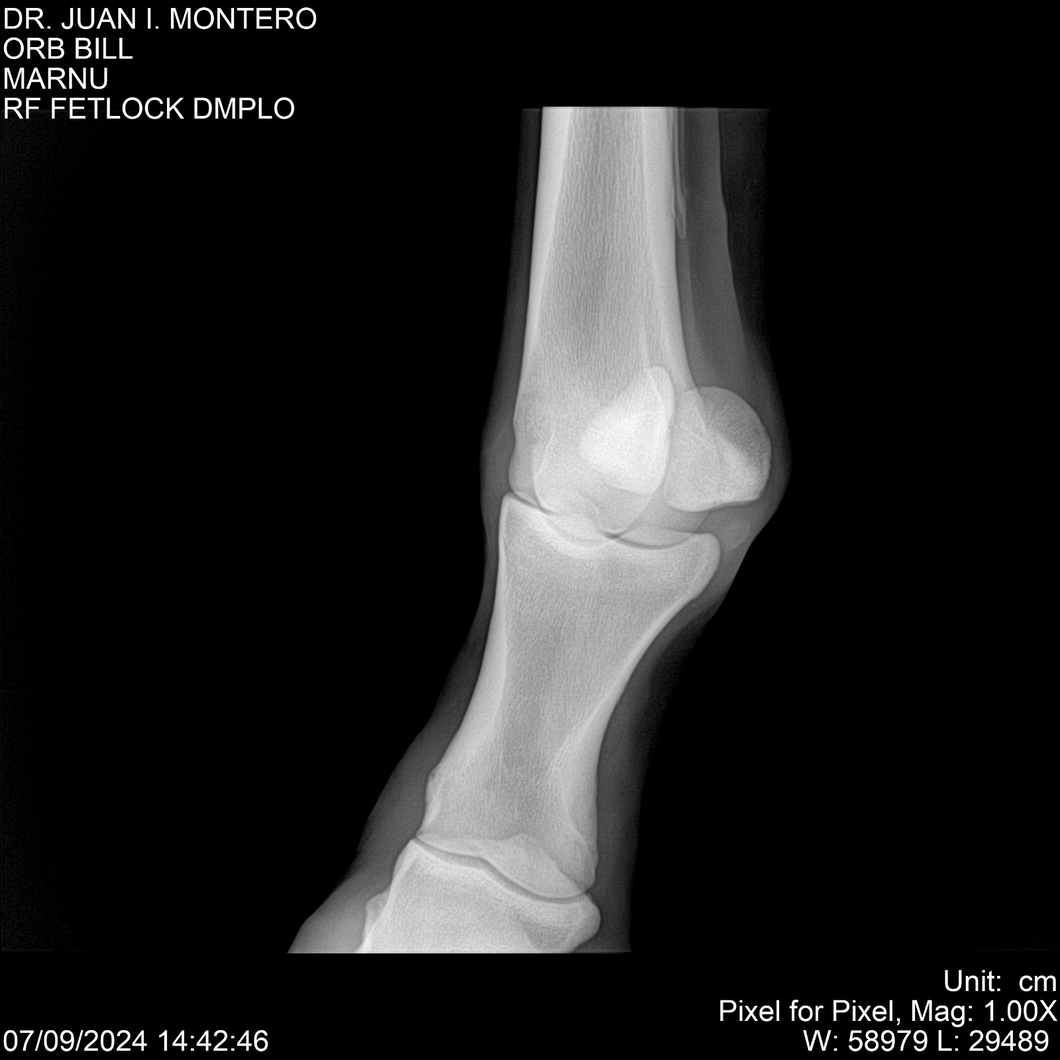

LOTE 7, ORB BILL 🔥 🔥 🔥 Lote Anterior Volver al remate Lote Siguiente Ficha Contacto Montevideo - Ficha del Lote Identificador: #282523 Categoría: Yeguarizos Montevideo - 83 Visualizaciones ClicData Contacto Empresa: Abelenda N. R., Walter Hugo Nombre*: Teléfono* : E-mail* : Mensaje Enviar Registrese gratis Este contenido Exclusivo está disponible sólo para usuarios registrados Ingresar